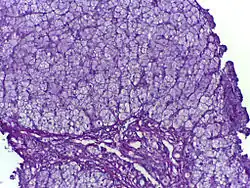

![]() | |

| Glycogen storage disease in hepatocytes | |